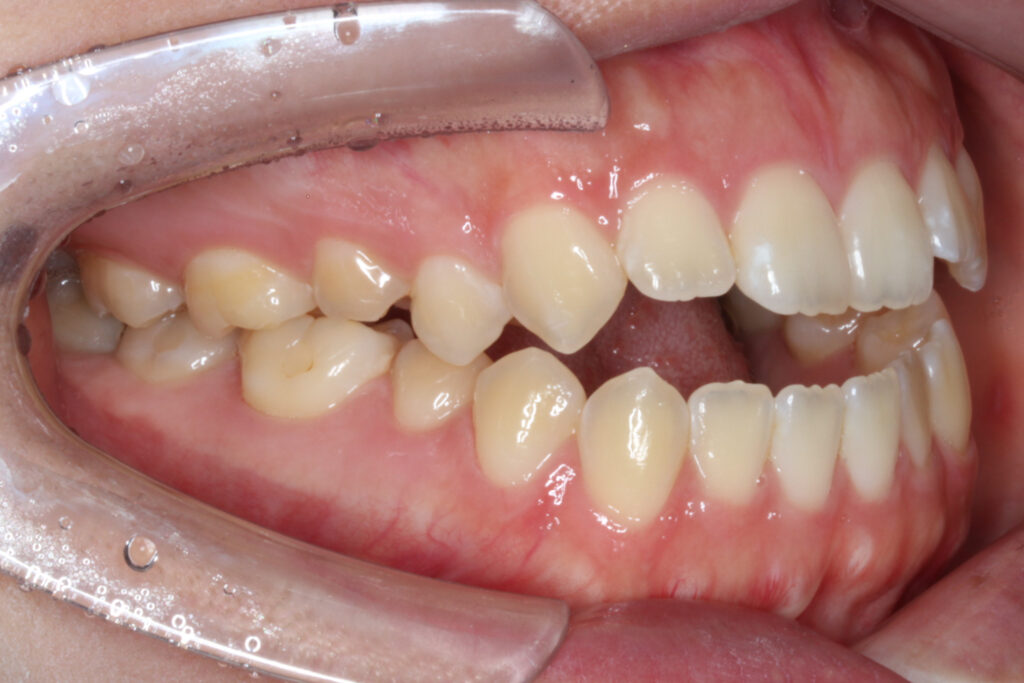

噛み合わせた際、上下顎の前歯が垂直的に被さらず空間ができている、「開咬」という歯並びの状態になっています。

下顎の骨格がやや前方へ位置しているため手術を併用した顎変形症としての治療も想定される噛み合わせの状態でしたが、

手術を行わずに矯正治療単独での治療を希望されました。

Before